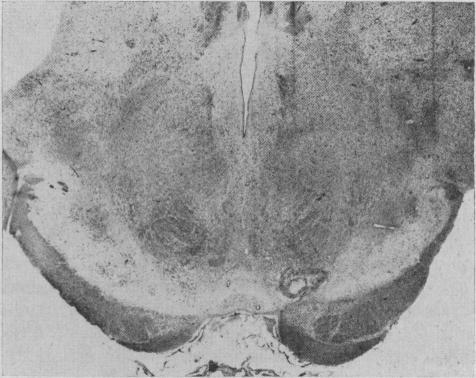

Monkeys inflicted with specific unilateral electrolytic lesions in the upper brain stem developed extrapyramidal disorders. Hypokinesia of the limbs was associated contralaterally with a lesion of the substantia nigra and depletion of striatal dopamine. Choreiform movements were observed in animals that had, contralaterally, a lesion severing the most dorsomedial fibres of the cerebral peduncle and the rubro-tegmentospinal tract, associated with depletion of striatal serotonin. Monkeys showing sustained postural tremor and hypokinesia had lesions affecting these three tracts contralaterally and loss of striatal dopamine and serotonin on the lesion side. Of many drugs tested, only harmaline and harmine affected the dyskinesias. The nigrostriatal fibres appear to be dopaminergic; the cerebral peduncular (dorsomedial) fibres, serotoninergic. The role of striatal dopamine and serotonin in the control of normal movements and posture of the limbs represents the first directly demonstrated function of these amines in the central nervous system.

在上脑干遭受特定单侧电解损伤的猴子出现了锥体外系疾病。肢体运动减少与黑质损伤及纹状体多巴胺耗竭对侧相关。在对侧有损伤切断大脑脚最内侧背侧纤维和红核 - 被盖脊髓束且伴有纹状体5-羟色胺耗竭的动物中观察到舞蹈样运动。表现出持续性姿势性震颤和运动减少的猴子对侧这三条束均有损伤,且损伤侧纹状体多巴胺和5-羟色胺缺失。在测试的多种药物中,只有骆驼蓬碱和骆驼蓬灵影响运动障碍。黑质纹状体纤维似乎是多巴胺能的;大脑脚(内侧背侧)纤维是5-羟色胺能的。纹状体多巴胺和5-羟色胺在控制肢体正常运动和姿势中的作用代表了这些胺类在中枢神经系统中首次直接被证实的功能。